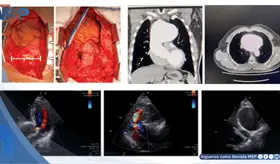

La inmunización antigripal disminuye los eventos cardiovasculares en un 34% durante el año posterior a su administración, mientras que la vacuna de la Covid-19 atenúa las complicaciones tromboembólicas